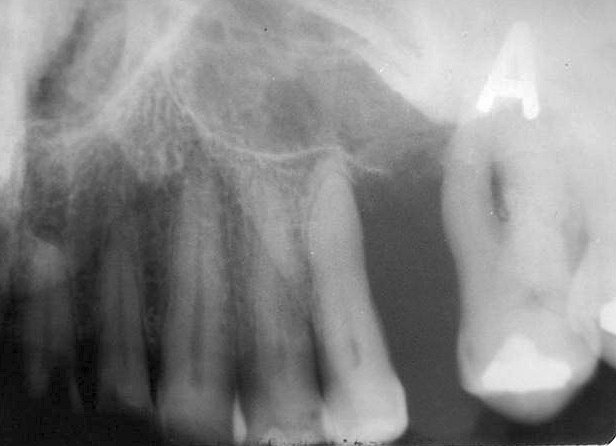

- Πιθανές επιδράσεις στα παρακείμενα δόντια: μετατόπιση, απορρόφηση ριζών και απώλεια της lamina dura.

- Αρχικά η βλάβη απεικονίζεται σαν μονόχωρη διαύγαση, με την αύξηση της αλλοίωσης μετατρέπεται σε πολύχωρη με τη μορφή της κερήθρας.

- Η βλάβη έχει ακανόνιστο σχήμα, συχνά με ασαφή όρια.